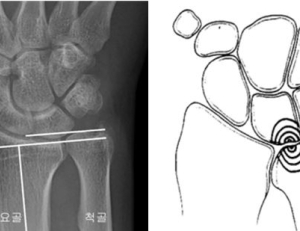

- 손흥민 '손가락 탈구', 완치까지 얼마나 걸리나

- 영국 프로 축구 무대에서 활약하는 손흥민 선수, 지난 2월 아시안컵 준결승을 앞두고 손가락 탈구 부상을 겪었다. 소속팀 복귀 후에도 손가락에 붕대를 감고 경기에 나서고 있는 손흥민은 언제쯤 붕대를 ...